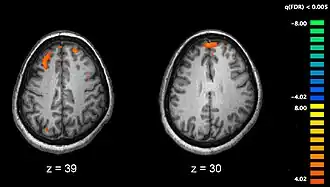

Schizophrenia has a fairly strong genetic component, although that is just one of a number of causes. Hypotheses for why schizophrenia emerges in some individuals but not others include an infection before birth, exposure to toxic substances, particularly drugs, and other disturbances of fetal development. Neurologically, there are some subtle but detectable differences in brains of people with schizophrenia. There is slight shrinkage in overall volume, and certain dopamine pathways also undergo chemical alterations.